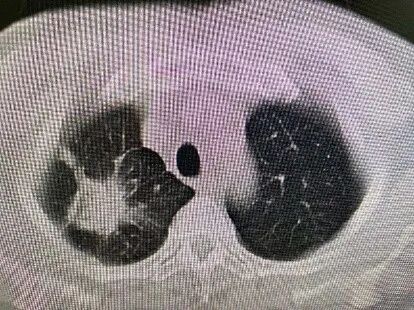

2021年1月,在病情趋于平稳、全身癌细胞控制良好的时候,肿瘤科针对杨先生肺内较大肿块进行了射频消融治疗。5个月后常规复查CT,发现做过消融治疗的肿块增大并且实性成分增多。医生心头一紧,难道是肿瘤再次发生进展了吗?

图片

治疗前dCJ帝国网站管理系统

射频消融后2个月dCJ帝国网站管理系统

射频消融后5个月dCJ帝国网站管理系统

病理报告:(肺穿)送检组织以纤维成分增生为主出血慢性炎伴大片坏死,另见少量肺组织。